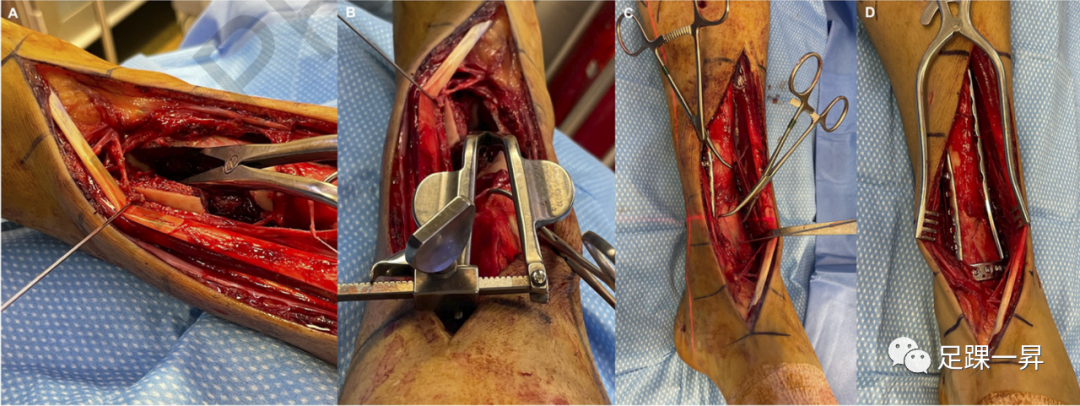

Pilon骨折手术的标准前路方法已得到充分描述。后侧入路也有很好的描述,可以在传统固定中发挥补充作用,直接复位和/或固定特定骨折碎片,并松解嵌顿的软组织结构。部分关节(OTA/AO型-43B)的手术入路相对简单,由移位的关节碎片区域决定。完全性关节(OTA/AO型-43C)损伤需要根据原发骨折线的位置以及关节面压缩区域采用个体化方法。已经提出了各种详细描述骨折复位和固定的手术技术。通常,具体的前路切口和肌腱间隔是基于前外侧(Chaput)和内侧骨折块之间骨折线的位置; 通过这些骨折块的间隙可以进入后方和进入压缩区域(图5)。直接内侧入路可用于支撑内侧柱避免内翻塌陷。

△图示Pilon骨折的术中照片,其中Chaput骨块和内侧骨块之间的骨折线被“翻书样打开”,以便于更靠后地接近压缩区域。一旦后侧复位工作完成,将Chaput骨块和内侧骨块复位并进行固定。

一项关于Pilon骨折手术入路的系统综述发现,与后外侧和前内侧入路相比,直接前路和内侧入路的并发症发生率较低,包括伤口并发症和骨不连。在另一项评估手术入路对Pilon骨折术后感染风险影响的研究中,未检测到相关性。已报告的并发症发生率差异可能是由于软组织的状况和血供所致。每种骨折和患者都必须单独考虑,以优化关节复位和软组织愈合。